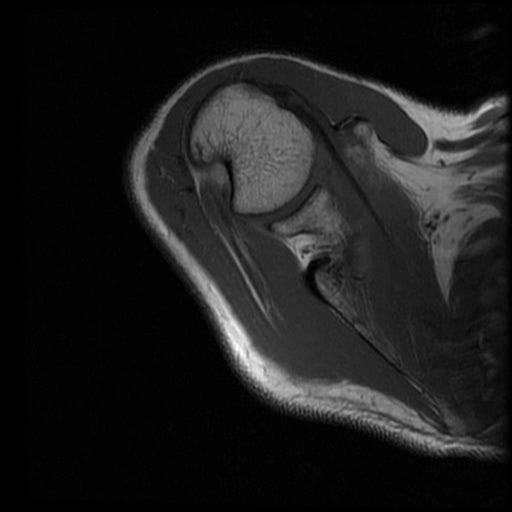

Tổn thương Bankart (Bankart Lesion)/ Rách sụn viền trước dưới